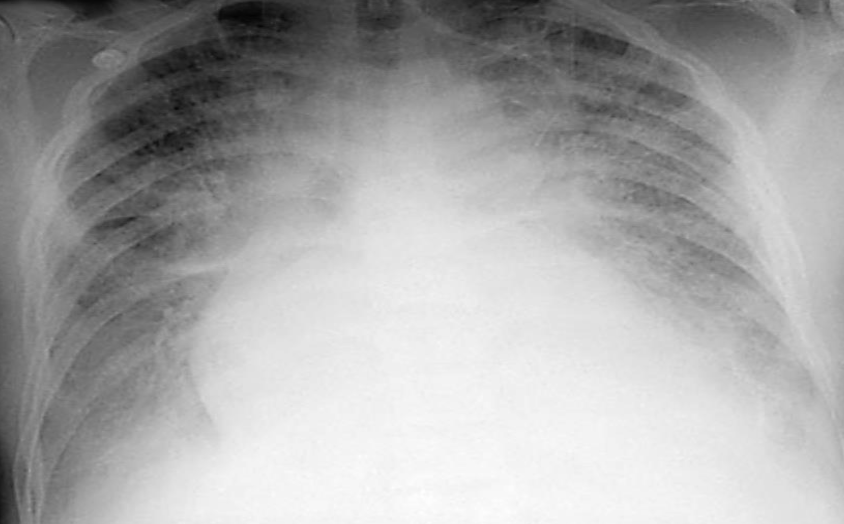

-Chest X ray of a 40 year old man

-HTN since 15 years

-Presents with acute dyspnea

-B.P. : 160/110

-Chest : Bilateral crepts on auscultation

-JVP: Raised

Q1: What’s your clinical diagnosis? Congestive heart failure.

Q2: name 2 abnormal findings in the chest x-ray? Cardiomegaly, pulmonary edema.

Q3: what investigation will give you more information about this cardiac condition? Echo.

Q4: What’s the cause of crepitation on auscultation? Pulmonary edema.

Q5: what immediate treatment will you give to this patient? Name any 2. Lasix, oxygen.

Q6: while this pt is in the ER, in what position should you put him? On 45 degree position.